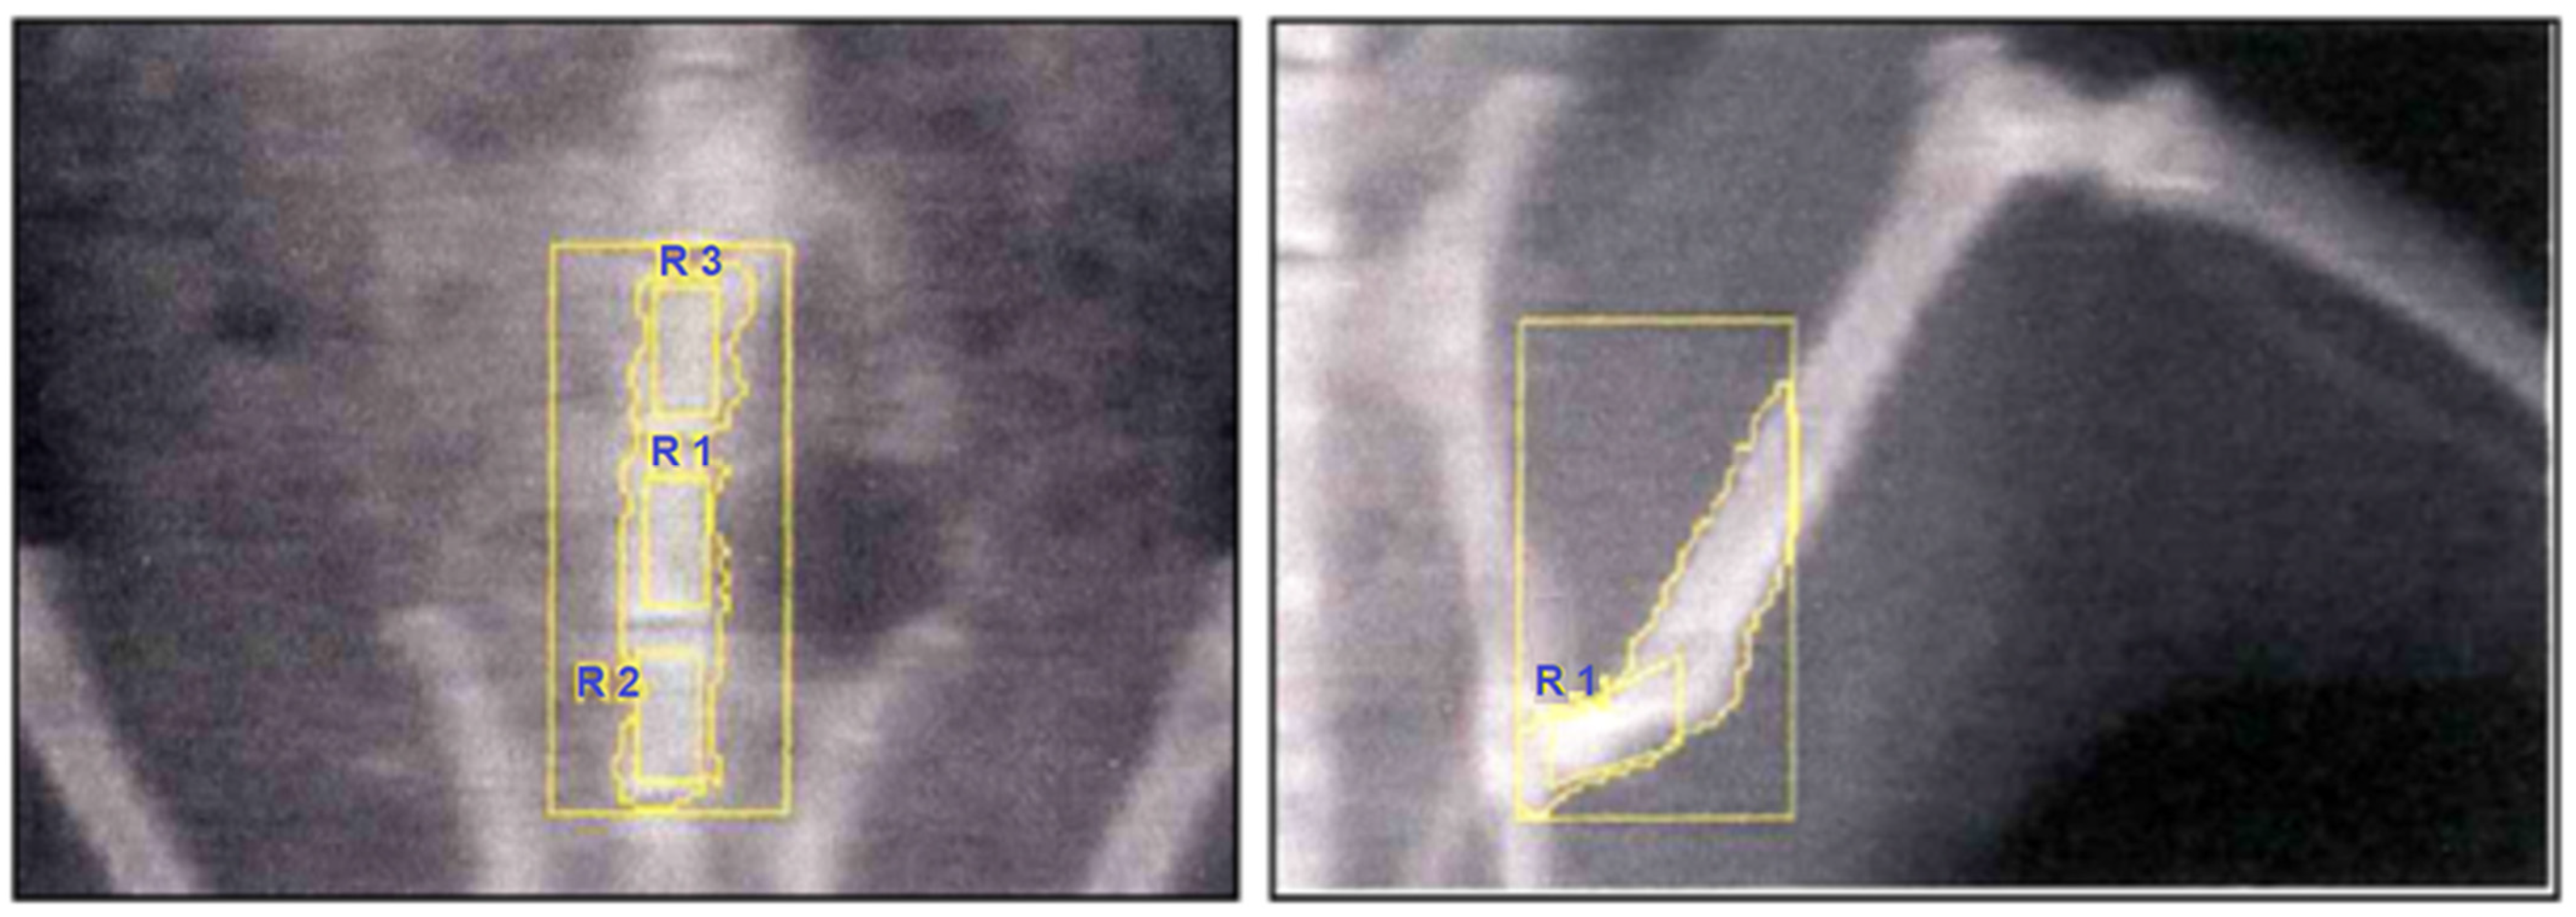

At the end of the treatment period, bone mineral density (BMD) was measured under ketamine anesthesia (50 mg/kg, i.p.). Dual-energy X-ray absorptiometry (DEXA; Hologic QDR-4500A, Waltham, MA, USA) equipped with a small-animal software program was used. High-resolution scans were performed at two anatomical sites: the proximal femoral diaphysis of the left hind limb and the lumbar vertebrae (Figure 2).

Figure 2. Representative DEXA scans of rat skeleton. (Left) Lumbar vertebrae with designated regions of interest (R1–R3) for BMD measurement. (Right) Femoral region with the selected ROI for femoral BMD determination.